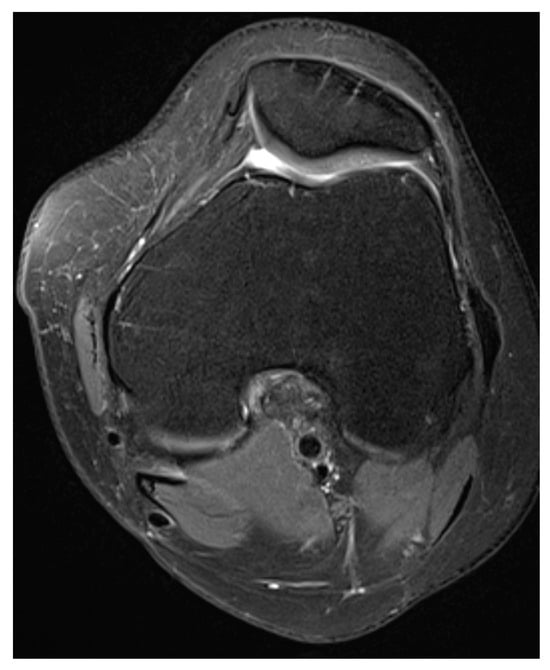

Medial Patellofemoral Ligament and Lateral Patellofemoral Ligament Reconstruction after Tibial Tuberosity Transposition in a Young Woman with Patellar Instability